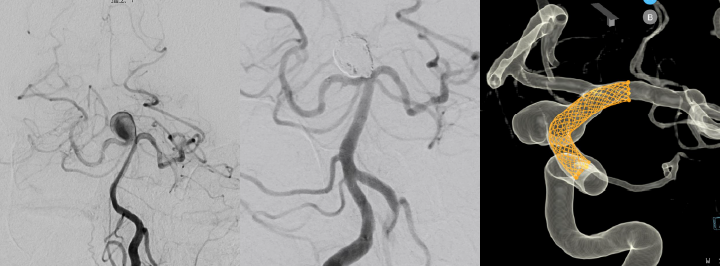

従来は治療が難しかった脳血管疾患に対しても、血管内治療はデバイスの進歩が著しい領域であり、治療選択肢が増えてきています。例えば、大型/巨大脳動脈瘤などでは、従来の標準的な方法(クリッピング術やコイル塞栓術)のみでは治療困難な場合があります。当科では、各種バイパス術を駆使した脳動脈瘤治療を積極的に行ってきた実績がありますが、最近ではそれに加え、フローダイバーターステントなどの新規治療法も加わり、より多彩な治療の実現が可能となっています。高度な治療ですが、当科には複数の専門医・指導医が在籍しており、先進的な血管内治療が可能な総合病院として、患者さんの病状などにより最適な治療を提供します。